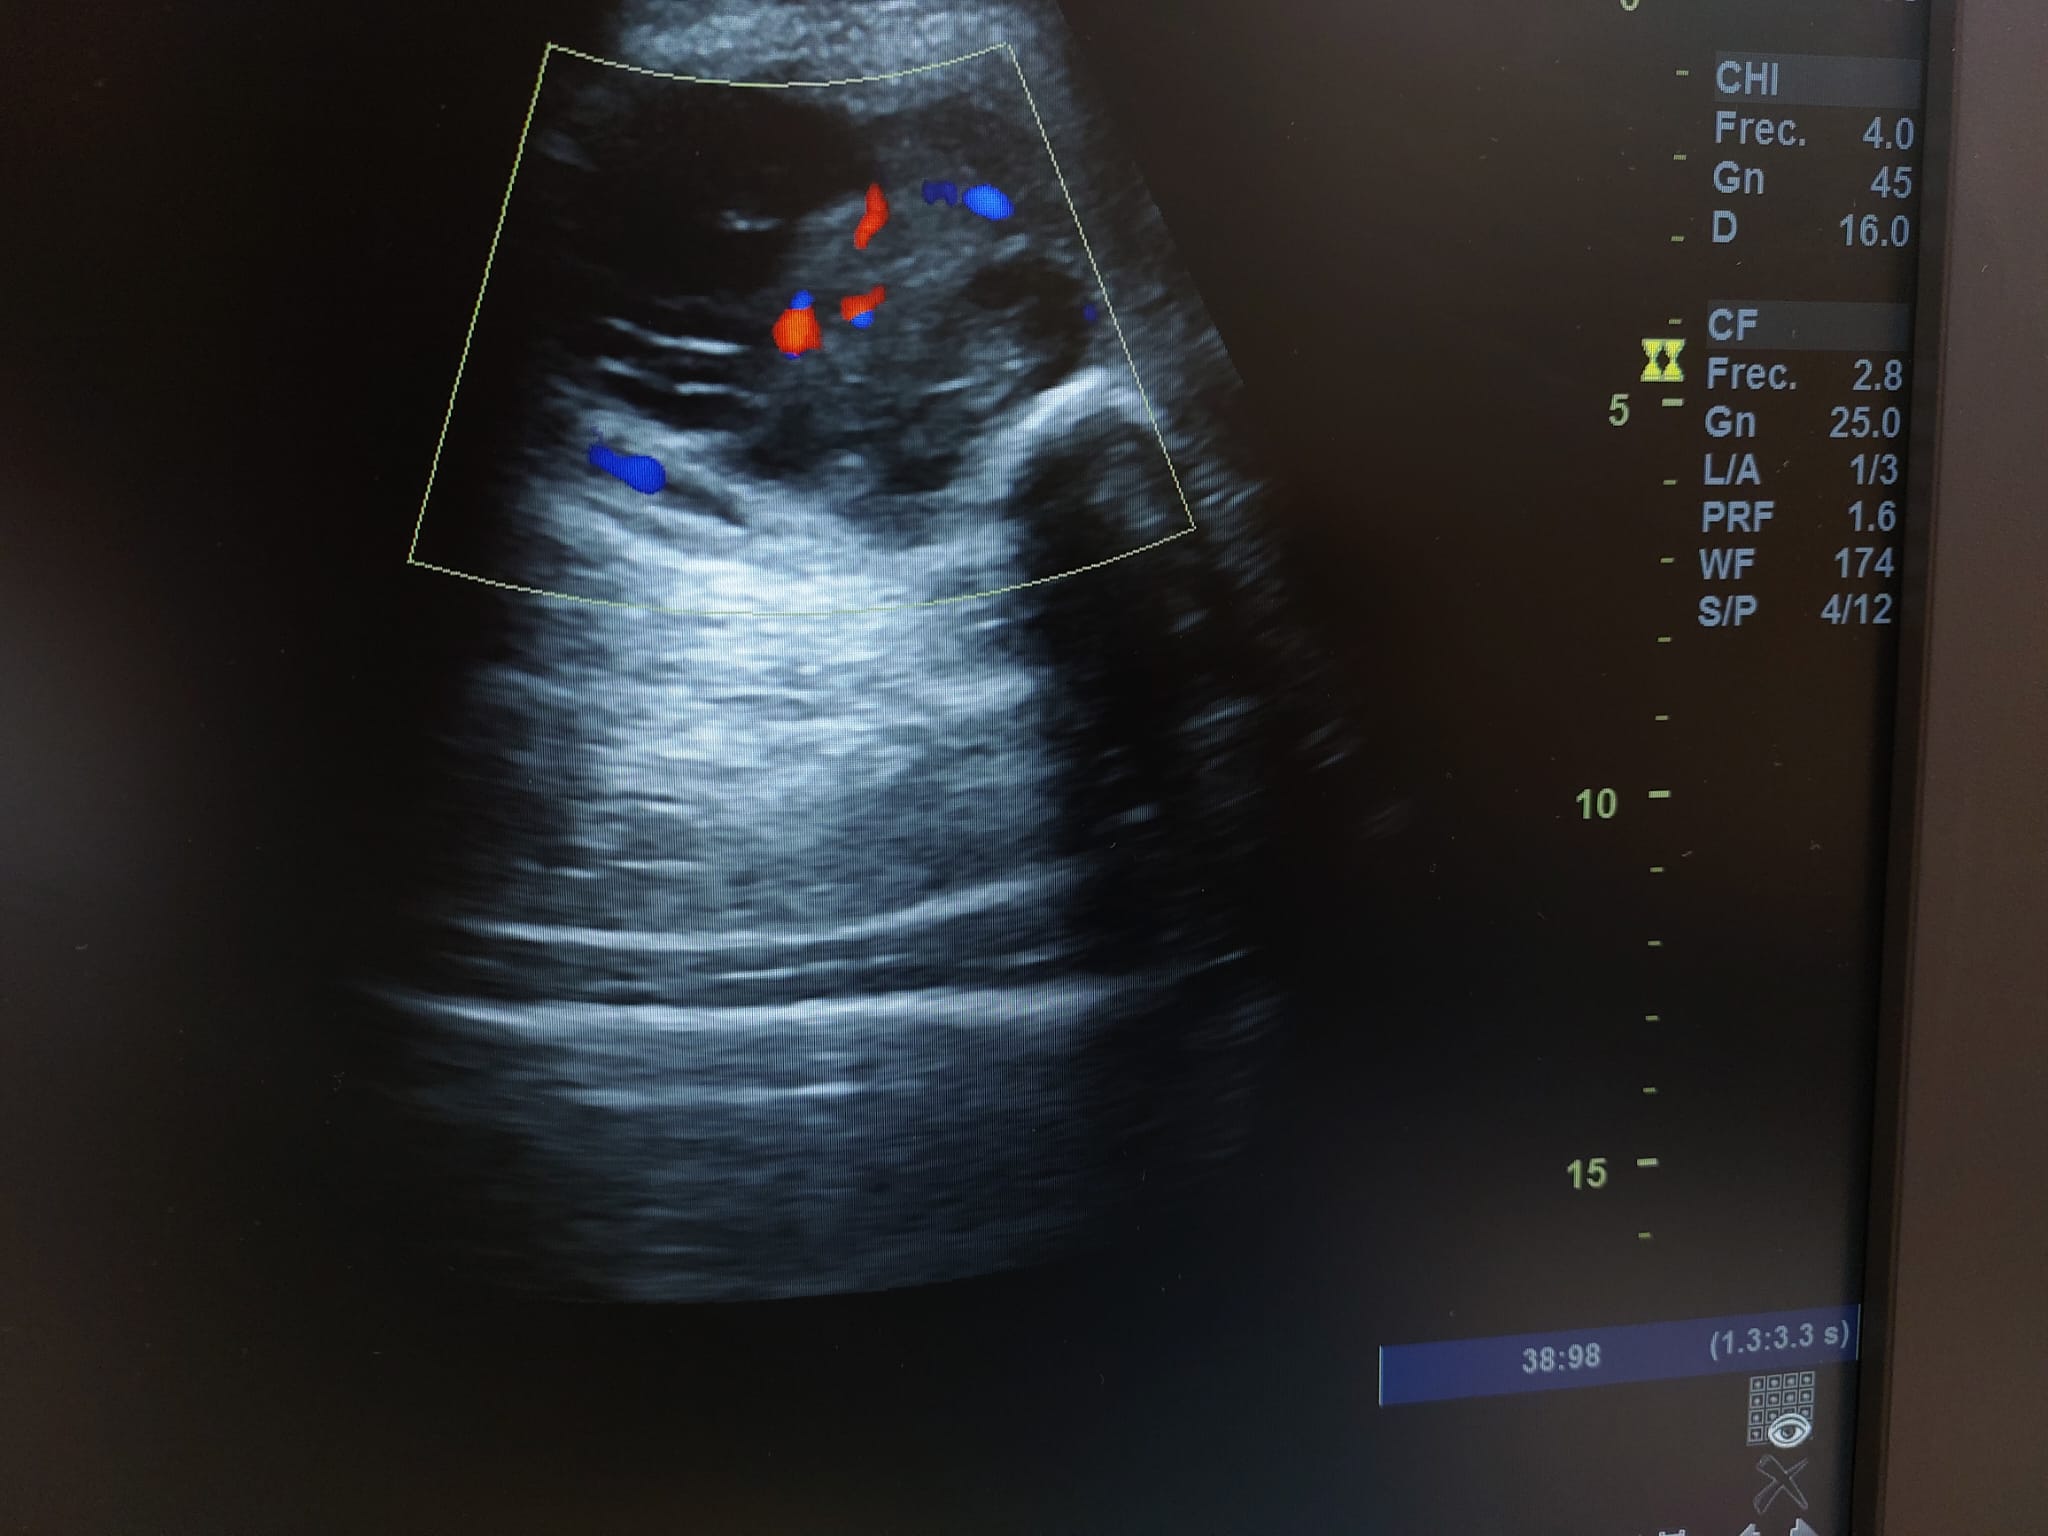

En el seguimiento se observa evolución tórpida sin mejoría clínica y en la ecografía de control se observa aumento notable de tamaño respecto al previo, estructura heterogénea de imagen anecoica con septos internos. Se aprecia edema intramuscular perilesional y captación al activar el Doppler. Se plantea la posibilidad de un hematoma sobreinfectado o, debido a su importante crecimiento, una probable etiología neoplásica. Tras hallazgos descritos en consulta, COT solicita de forma urgente la realización de RNM y biopsia de la lesión. Posteriormente, el resultado de las pruebas complementarias confirman diagnóstico de sarcoma histiocítico.